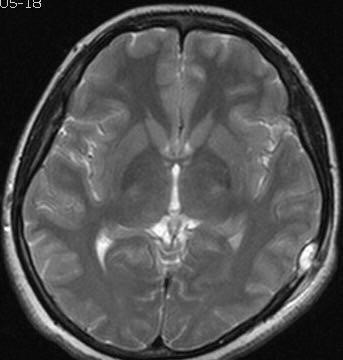

1.X线/CT:显示溶骨性破坏(边界清晰,局限性颅骨缺损,缺损边缘不规则呈“虫蚀样”改变,颅骨内外板受破坏,在病变组织内可见条索小骨影,病变周围可见软组织块影征象)。

2.MRI:评估软组织受累范围。